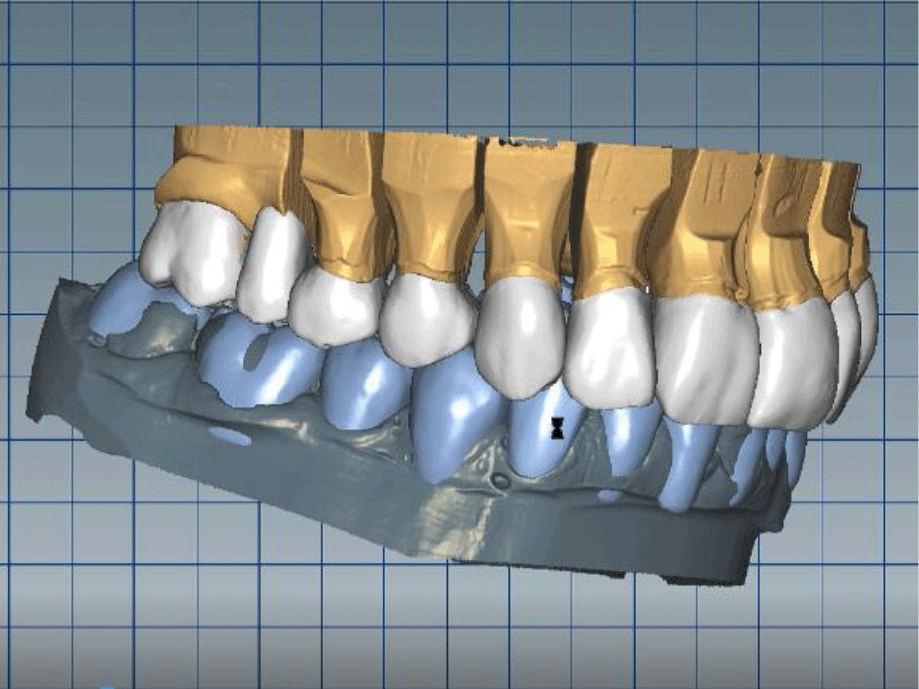

The cast gypsum models were scanned with a laboratory scanner and the obtained digital models were subjected to additional processing. Briefly, transfer of the morphological planning for the upper dentition (crown strategy) and for the lower dentition (digital wax up strategy, pontics) was performed (Figures 9 and 10).

26dd931c-41d3-478d-bec1-8cb211d0a4b8_figure9.gif

Figure 9. Clinical situation after upper preparation with increased VDO.

26dd931c-41d3-478d-bec1-8cb211d0a4b8_figure10.gif

Figure 10. Digital design on both jaws.